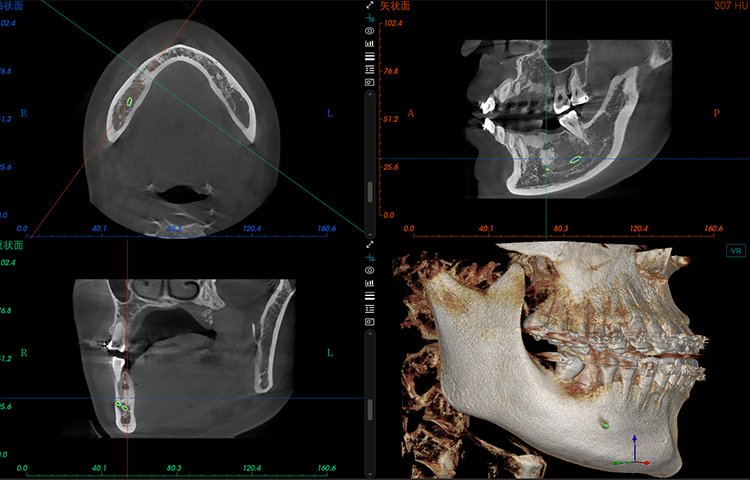

El software de diagnóstico 3D líder de Meyer y el sistema de análisis ortodóntico inteligente adoptan un diseño de UI modular, lo que hace que las funciones del software sean más cercanas a las necesidades clínicas y más fáciles de usar para los médicos, reduciendo significativamente el costo de aprendizaje.

Software de Diagnóstico 3D

MyDentViewer